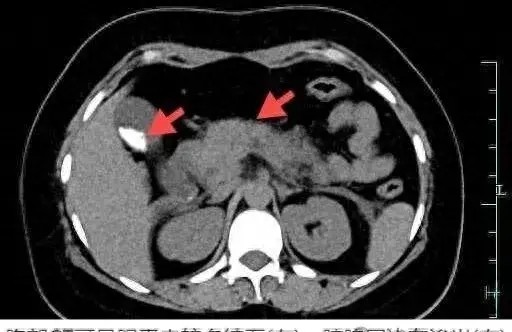

吃货们,你们可得悠着点儿!杭州这位姑娘因为一口气吃了四只大螃蟹,结果急性胰腺炎找上门,差点儿把小命搭进去。螃蟹虽好,可不要贪杯哦!

医生说,螃蟹蛋白质和胆固醇含量高,一般人吃两只就差不多啦。别仗着自己年轻身体好,就胡吃海塞,到时候进了医院,哭的还是你自己。